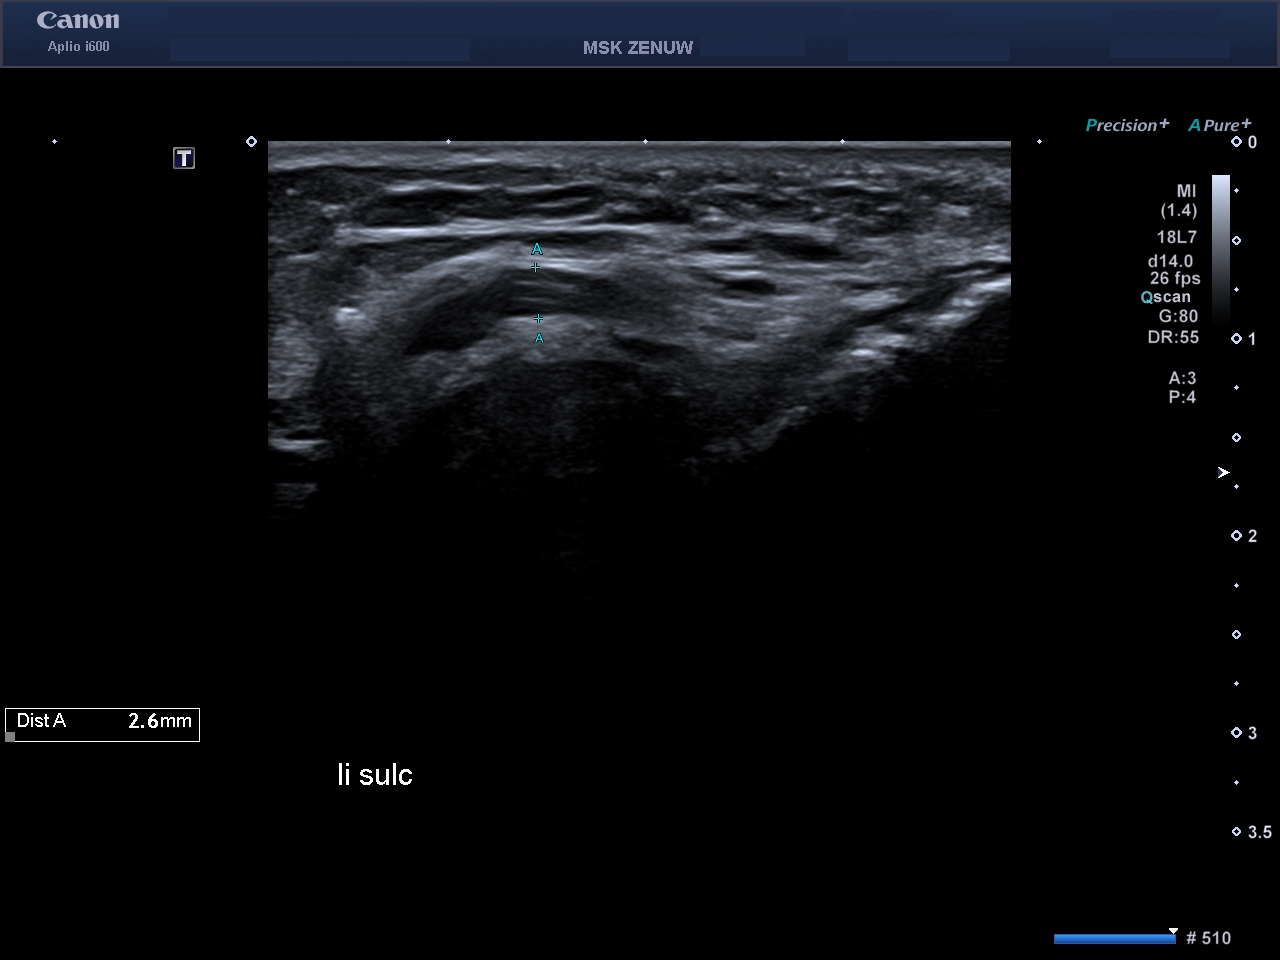

Представляємо вам клінічні випадки візуалізації періферійніх нервів на Aplio i800 з використанням високочастотного датчика 24 MHz. Ці приклади яскраво говорять самі за себе.